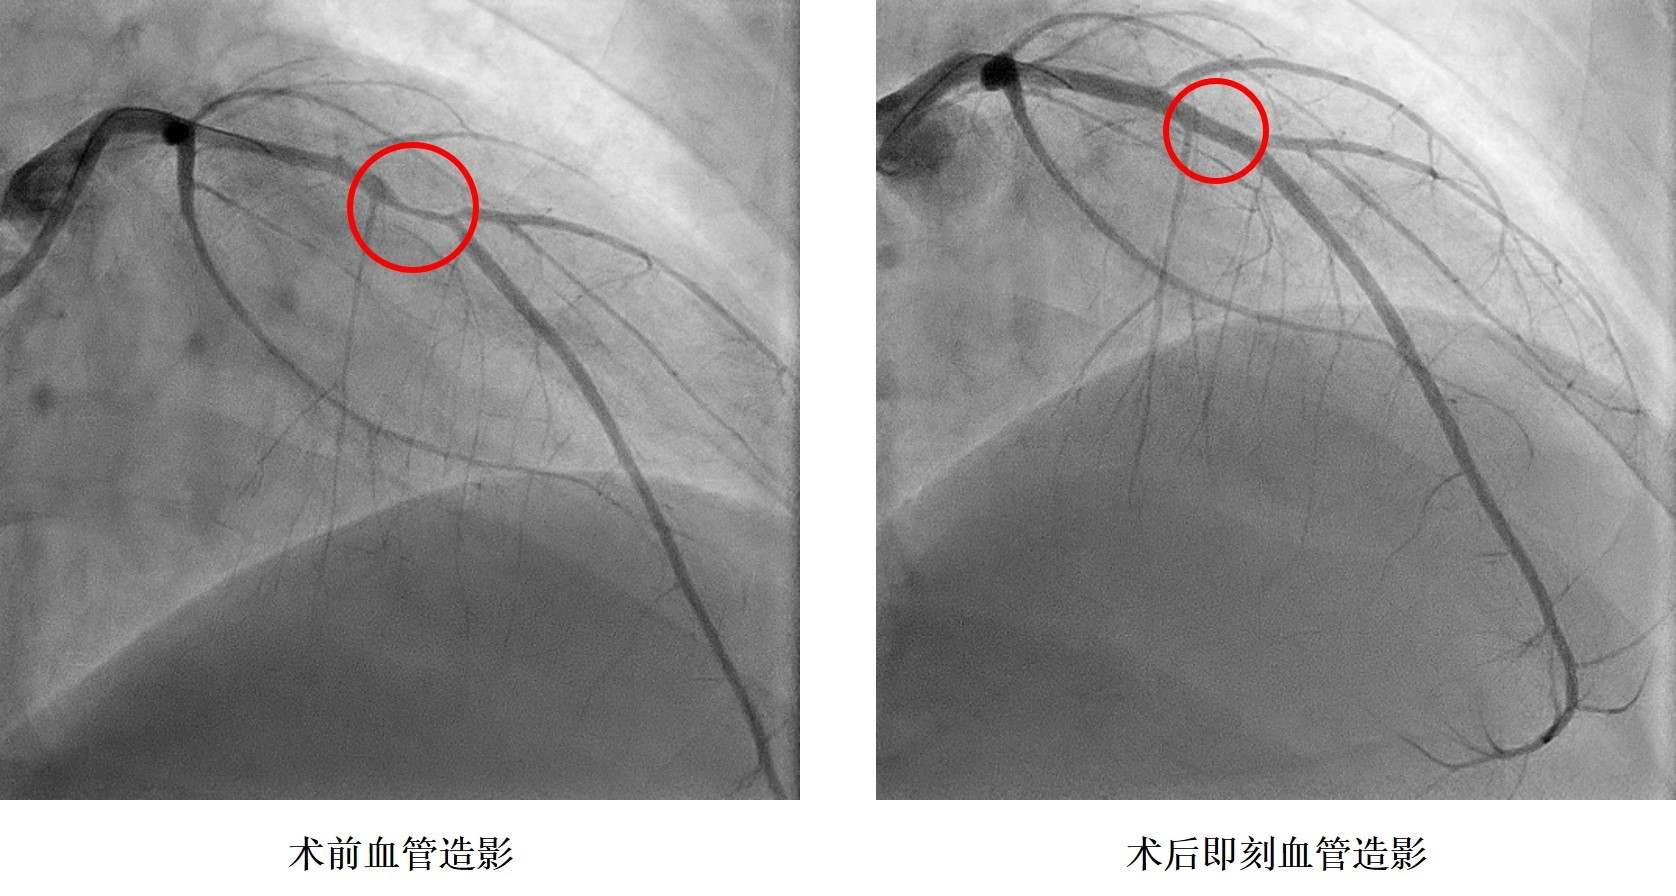

小浩在2019年9月6日晚飯時突感胸痛、胸口悶、呼吸困難,立即前往湖南省人民醫(yī)院胸痛中心就診,診斷為急性心肌梗死,小浩被送往介入手術(shù)室,進(jìn)行急診造影后發(fā)現(xiàn)冠狀動脈血管嚴(yán)重狹窄,需要在體內(nèi)植入心臟支架。據(jù)了解小浩從14歲就開始了抽煙,還發(fā)現(xiàn)了高血壓,血壓最高200mmHg,卻一直沒有規(guī)律服藥治療。16歲讀完技校后的他開始過上了淘寶電商的生活,生活日夜顛倒,夜間修圖、改片,并頓頓燒烤,白天睡覺,缺乏運(yùn)動,這樣的生活維持了兩年本次。入院后同時發(fā)現(xiàn)了糖尿病,這一系列原因是導(dǎo)致小浩發(fā)生心肌梗死的罪魁禍?zhǔn)住?/p>

孩子還這么小,人生剛剛開始就要帶上心臟支架生活嗎?心內(nèi)科鄭昭芬主任組織團(tuán)隊進(jìn)行了會診,建議植入生物可吸收心臟支架。“我們本來不愿意植入心臟支架,但聽說有一種新型的心臟支架在植入體內(nèi)后幾年就能降解,就接受了!痹谡鞯眯『票救撕图胰送夂,心內(nèi)三科潘宏偉主任利用血管內(nèi)超聲指導(dǎo),順利植入生物可吸收心臟支架,拆除了小浩體內(nèi)的“炸彈”。